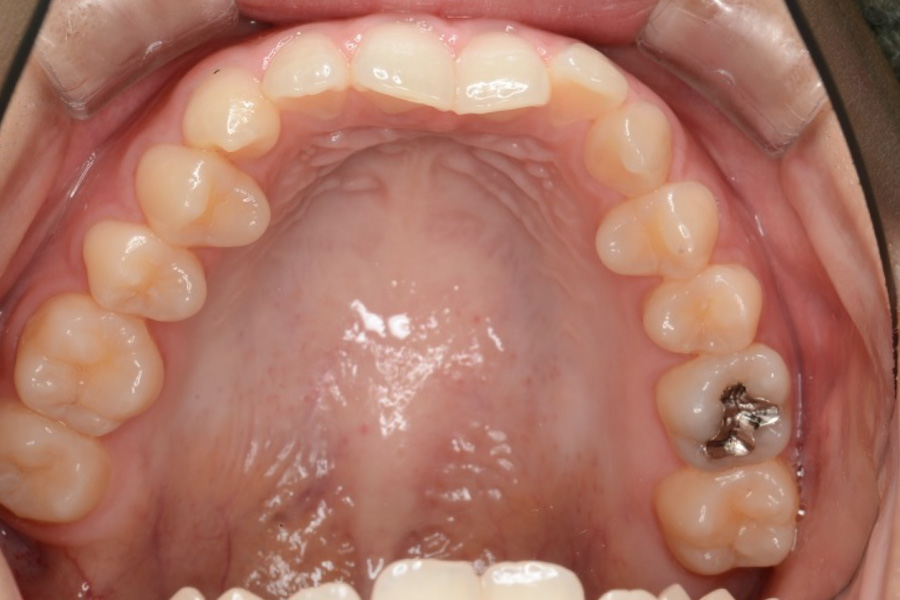

治療前

主訴 前歯で噛めない

治療内容 インビザライン矯正

非抜歯